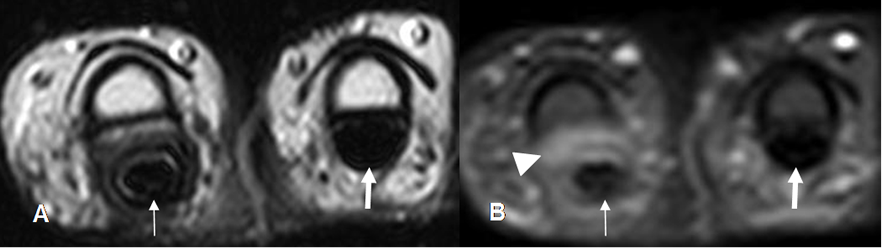

Fig 67. Lesión del mecanismo flexor.

A: RM axial en T2 y B: RM axial en STIR. Tendón flexor íntegro. (Flecha delgada). Separación del tendón de la falange media, por daño de la polea y presencia de tejido inflamatorio. (Punta de flecha). Comparar la posición del tendón normal, en el dedo adyacente. (Flecha gruesa).